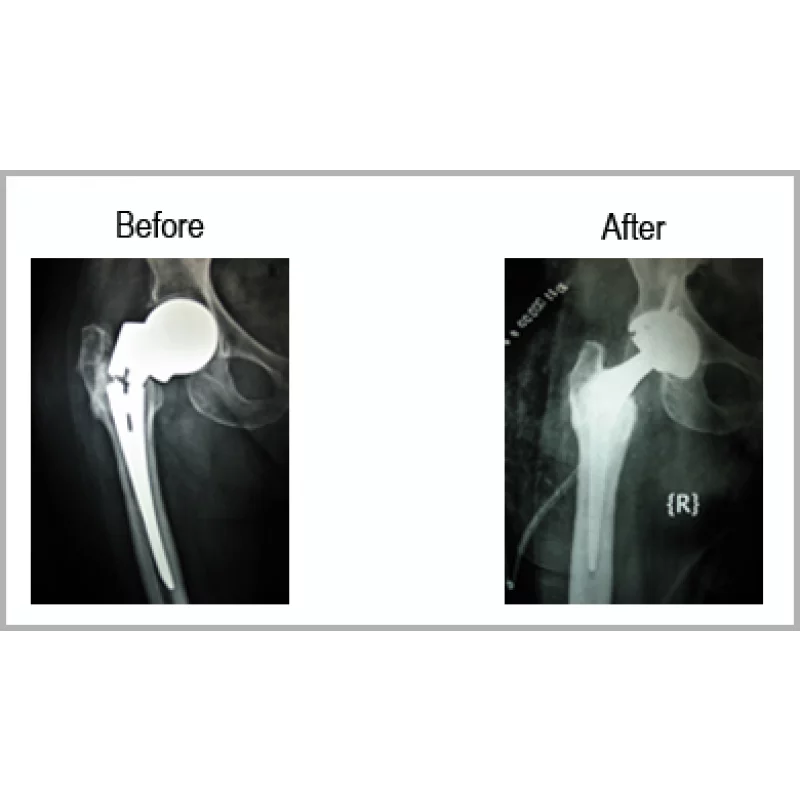

Implant Failure

A Female Aged 67 Years Operated Inform Of Prosthesis For Neck Femur Fracture Before 2 Years. She Was Not Able To Walk Because Her Metal Ball Was Broken. She Had Severe Pain Even While Moving Her Affected Hip.She Underwent Total Hip Replacement And Able To Move From The Same Day. She Is Absolutely Pain Free And Walking Without Support.... Read more